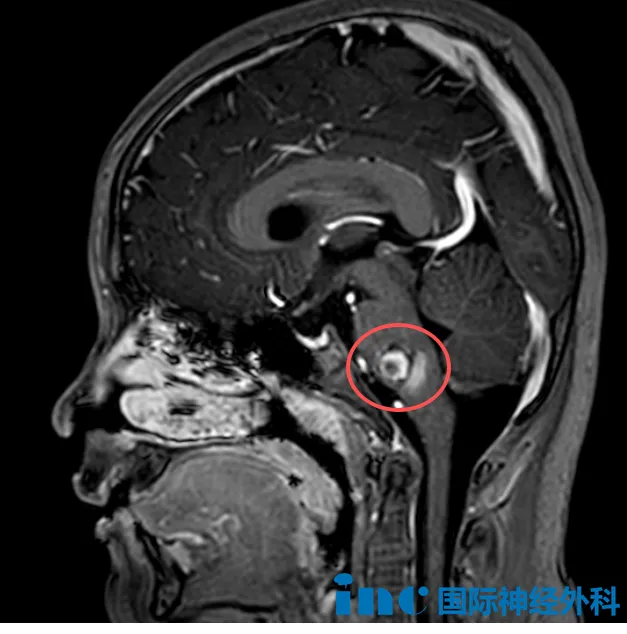

最新磁共振检查结果显示:脑干部位可见一个约16×11×14mm的“爆米花”状异常信号灶——这个盘踞在生命中枢的病灶,正影响着孩子的健康与未来。目前达恩主要表现为右侧肢体无力和轻度面瘫,其他神经功能尚属正常。

面对这个被称为“手术禁区”的脑干病变,达恩的家人在多方咨询后,了解到巴教授在该领域丰富的成功经验,决定为孩子争取手术机会。他们跨越千里来到中国,早早抵达苏州大学附属儿童医院,既怀抱希望,又不免对手术风险充满忐忑。